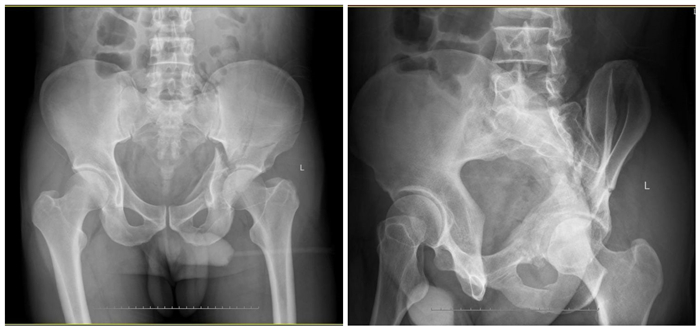

近日我骨一科就收治了一名因车祸伤至左侧髋臼双柱复杂骨折的病人。众所周知,骨盆髋臼骨折是创伤骨科最难的手术之一,髋臼骨折最复杂的类型(按Judet-Letournel 分型)就包括有前后柱的双柱骨折。

术前DR